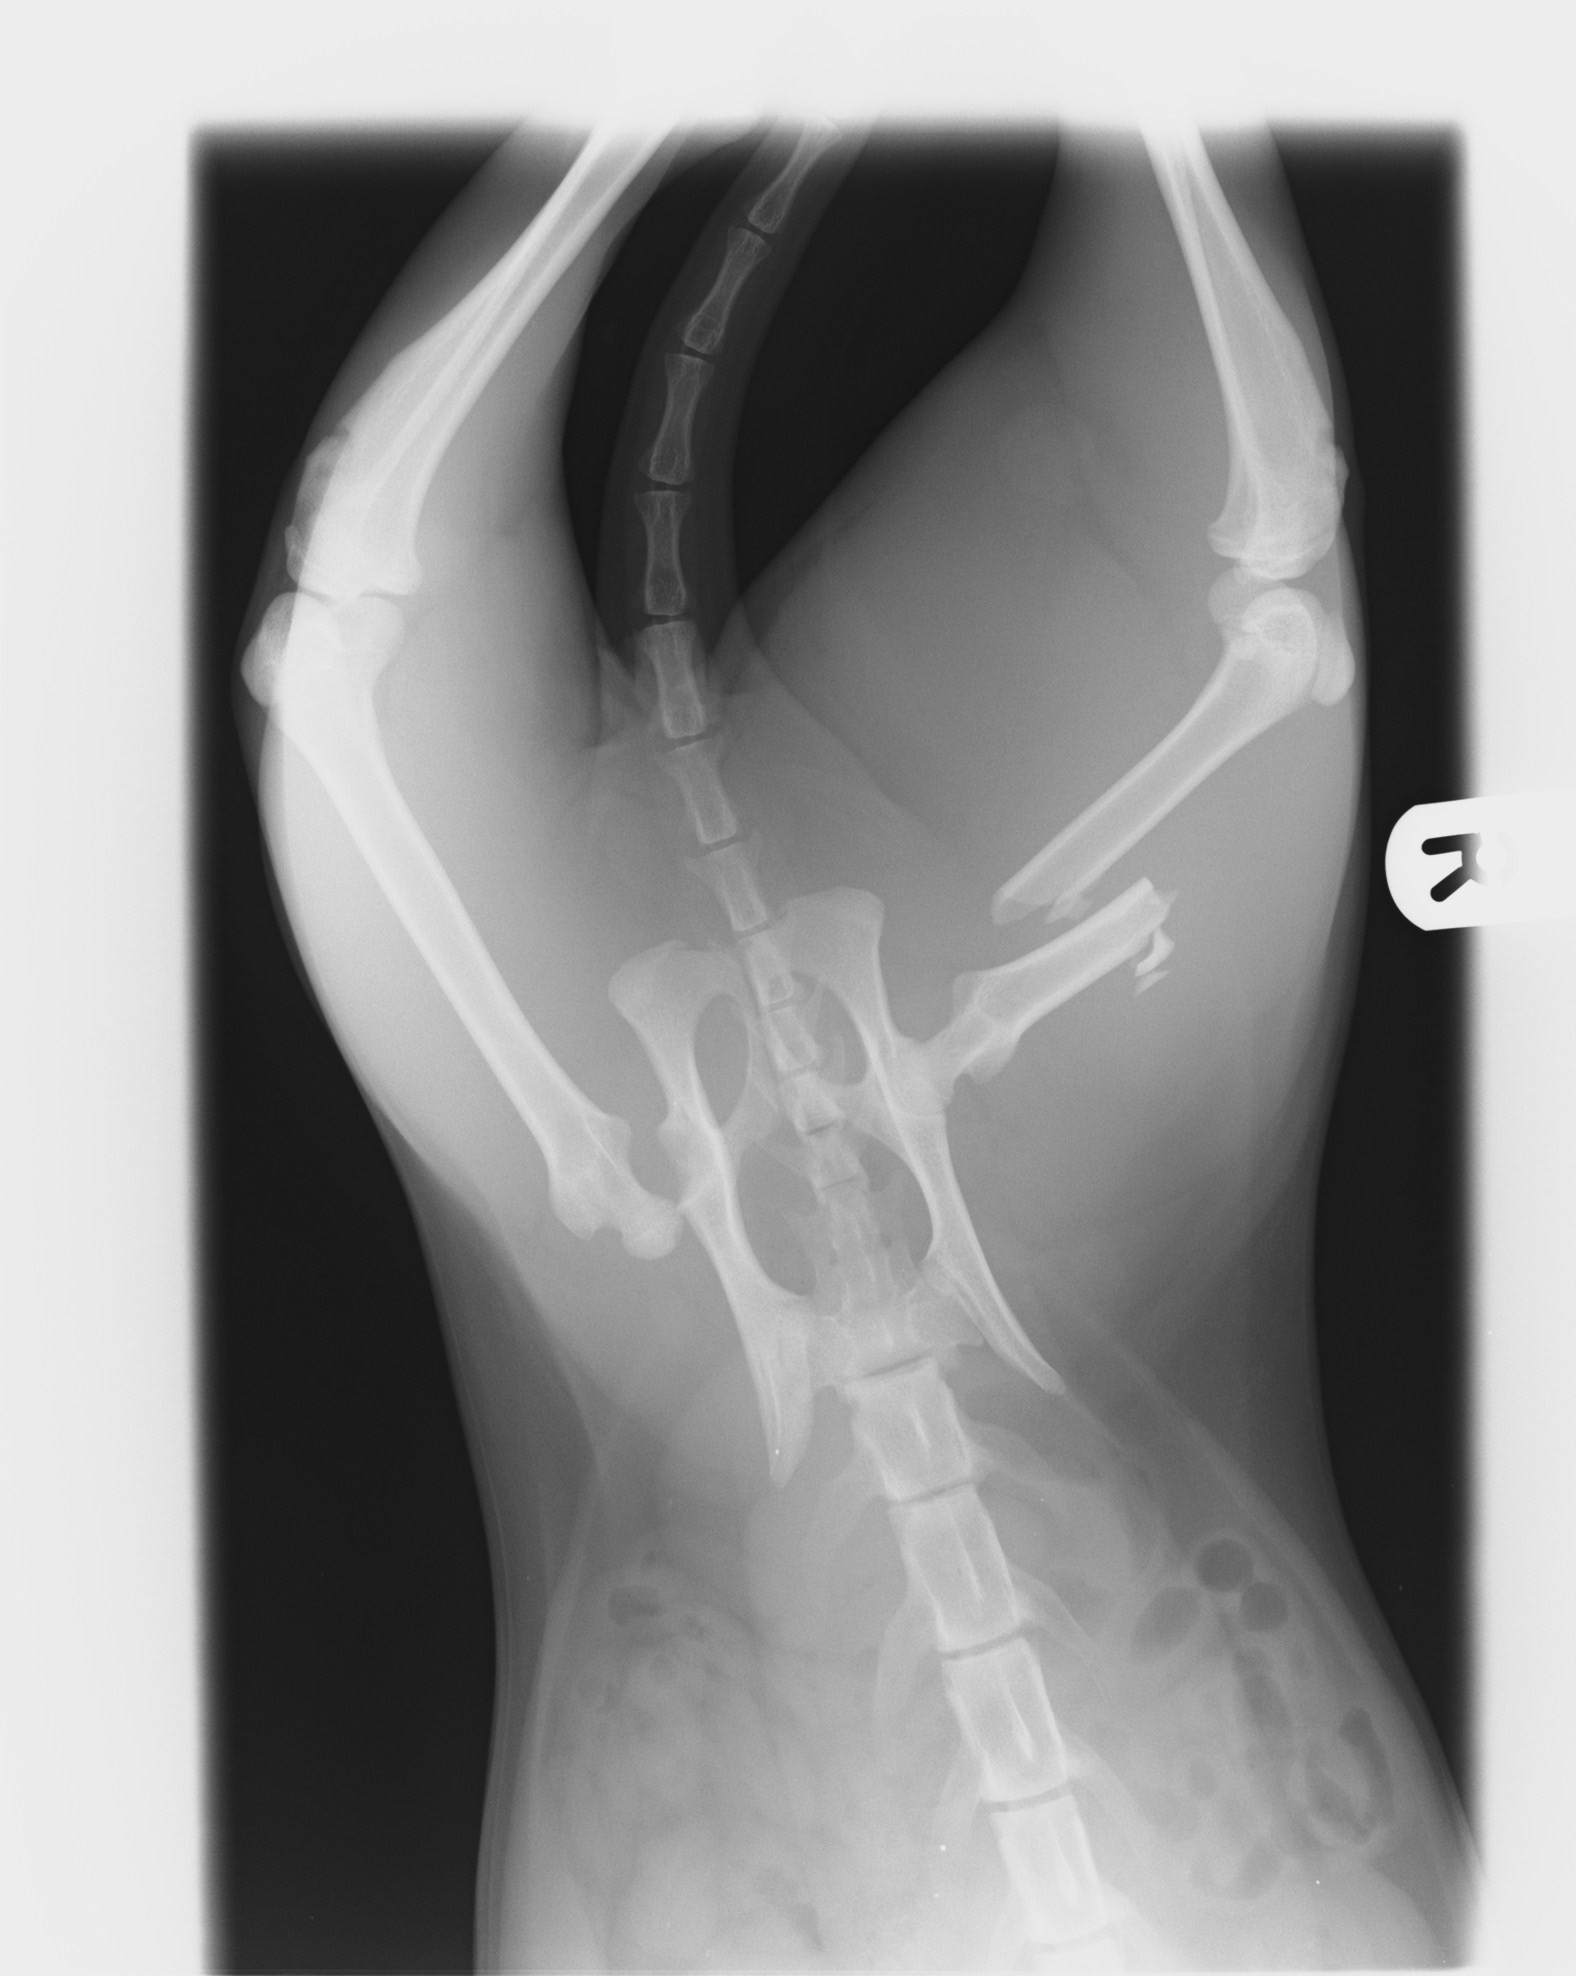

My name is Kaitlyn and I’m fundraising for our beloved cat, Sanza. He was recently hit and left on the side of the road near Shortlanesend. Sanza has serious injuries – his hip is dislocated and his femur is broken. The vets have told us he needs urgent treatment if he’s going to walk and live a pain-free life again.